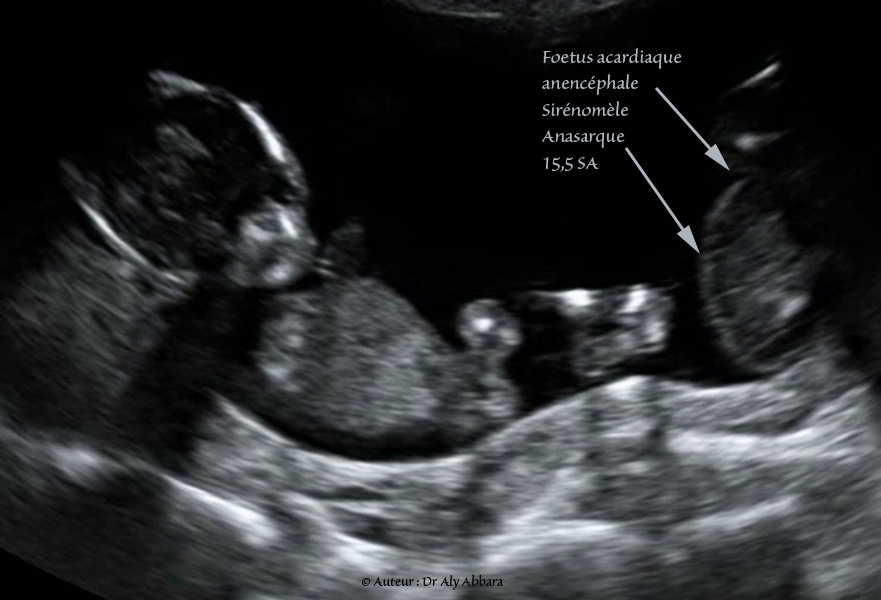

Jumeau Acardiaque Acardie Grossesse Gemellaire Monochoriale Biamniotique Echographie حمل توأمي مع وجود توأم منعدم القلب